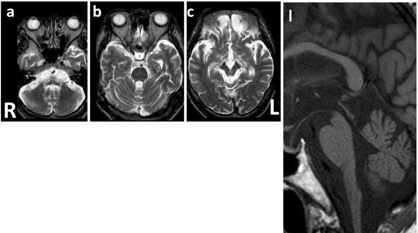

图 9 T2WI 可见明显的延髓萎缩 [a] 伴轻度小脑萎缩 [a~b],但脑桥基底部基本正常 [b],四脑室稍扩大 [b],中脑,特别是背侧,可见萎缩 [c];l:矢状位 T1WI 可见典型的蝌蚪状脑干萎缩,包括明显的颈髓-延髓萎缩,脑桥基底部完整,需注意,中脑被盖萎缩同样促成了「蝌蚪」的形成